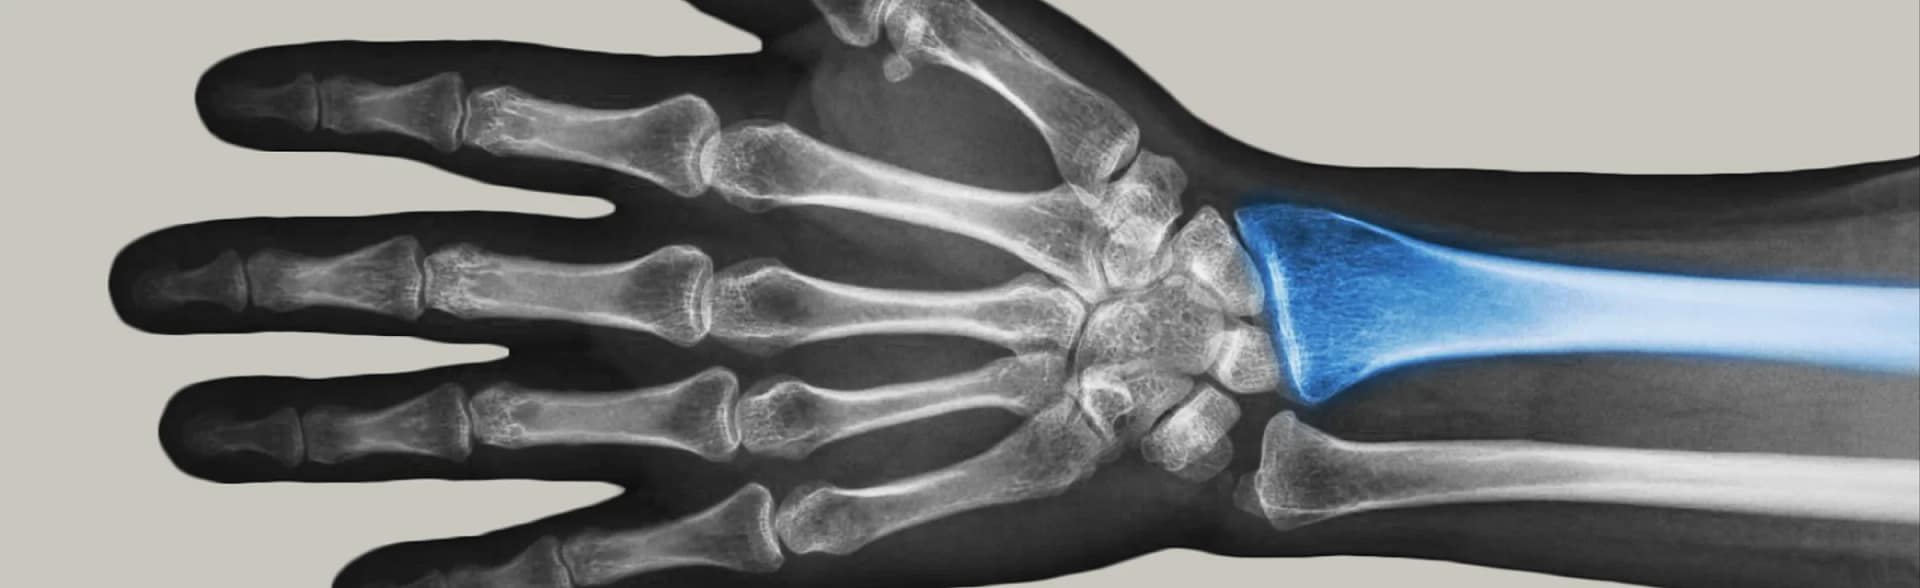

What are distal radius fractures?

The radius is the major bone in the forearm that makes up part of the wrist. A fracture or break in the distal radius generally occurs secondary to trauma, commonly from a fall from a standing height, but in some cases with higher energy. These fractures can be simple two-part fractures, but in some instances, the bone can fracture in multiple places. These breaks can lead to significant deformity and loss of function.

It is diagnosed by taking a careful history and performing a detailed examination. There are potentially other associated injuries of bones in the hand or the forearm, which the clinician will carefully exclude. Assessment will be made to ensure that the associated nerves and vessels have not been injured. X-ray, and CT imaging in selected cases, can be useful to exclude other potential injuries and to further assess the fracture particularly in cases where surgical management is required.